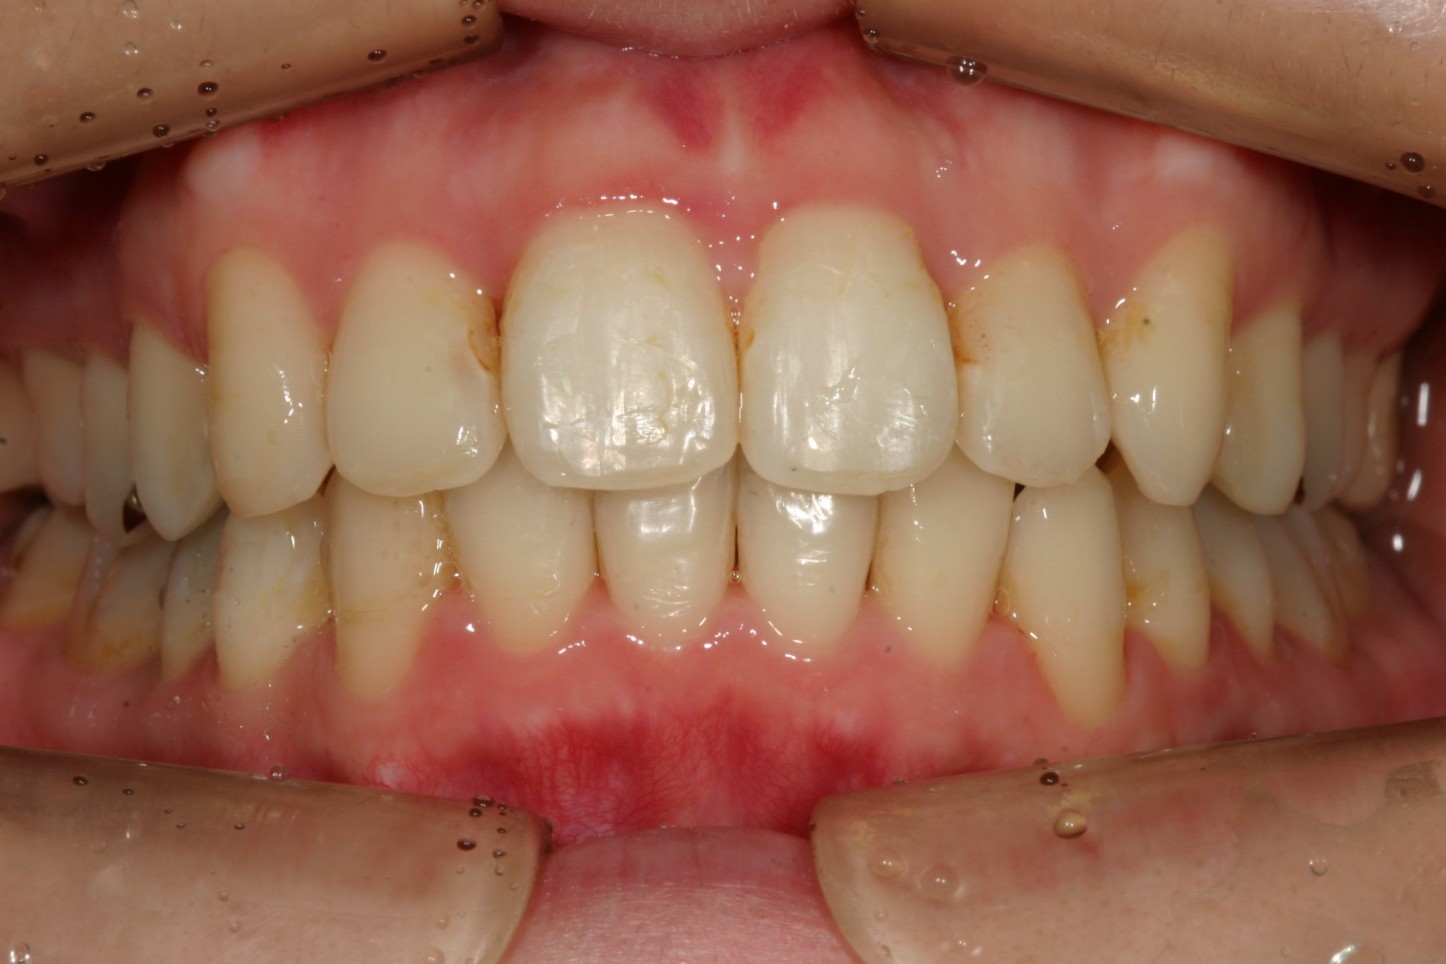

出っ歯感は残ったままです。

非抜歯でアーチも拡大され翼状捻転も改善しました。

下顎も非抜歯でこの様に綺麗なアーチになりました。

抜群のオーバージェットが得られました。